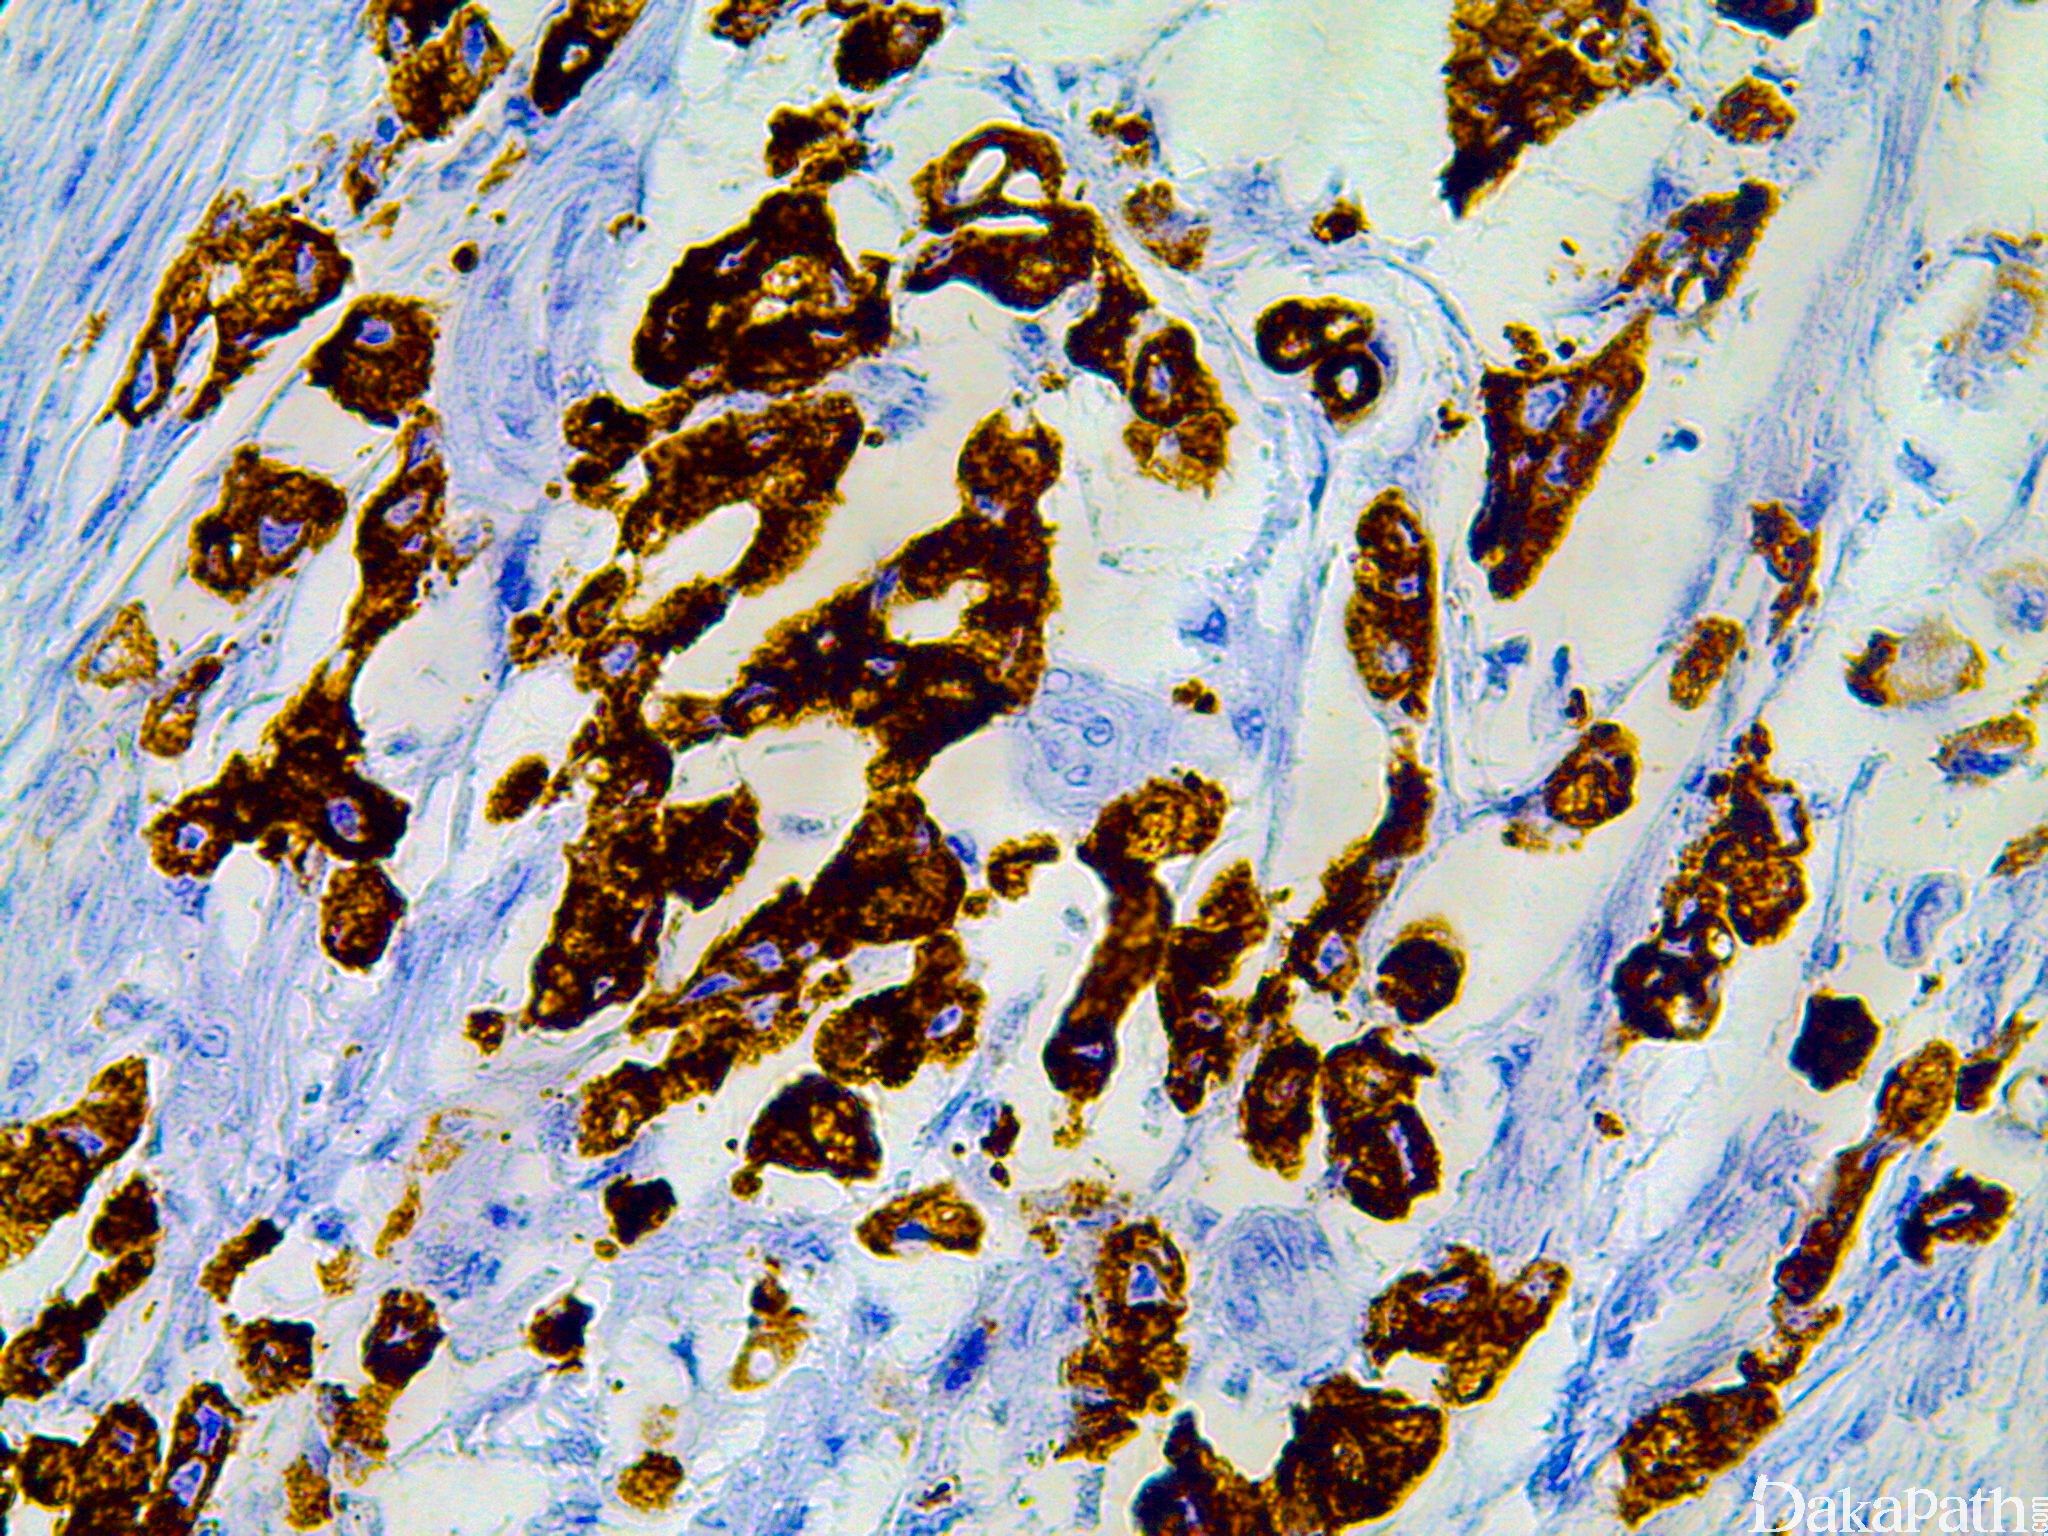

MUC2

由肠杯状细胞和呼吸道上皮产生,正常只表达于肠上皮,又称肠型黏液。

信号定位: 胞质